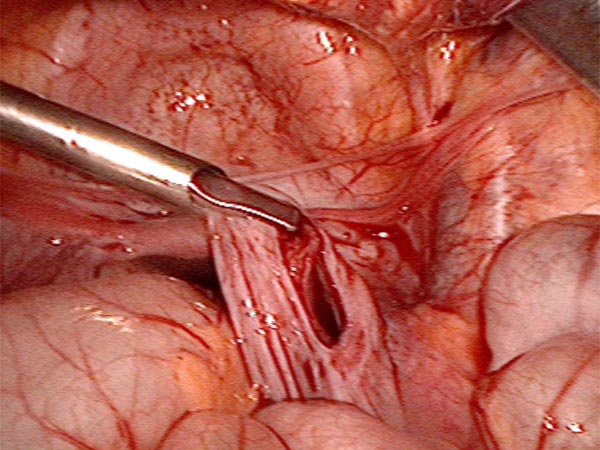

Image during laparoscopic resection: view from the umbilicus to the lower abdomen with some free fluid on the bladder. A large retroperitoneal cyst (lymphatic malformation) bulges in front.

The peritoneum to the posterior abdominal wall is opened and all the cysts are gradually dislodged and removed.